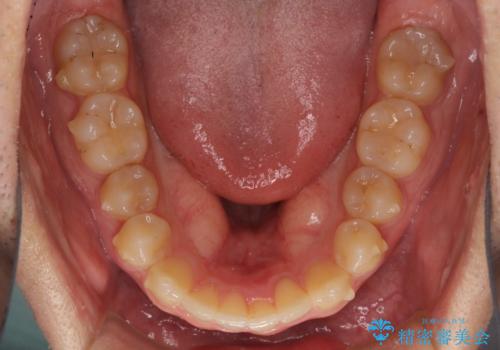

- 上下前歯のデコボコと深い咬み合わせを気にして来院された患者様です。

インビザラインによる上下歯列の拡大と、IPR(歯と歯の間を削る)にるスペースの獲得により、前歯のデコボコとディープバイトを改善することとしました。

もう少し下の前歯を整えたかったのですが、患者様の治療を早く終了させたいという希望により、細かい叢生を残しての終了となりました。